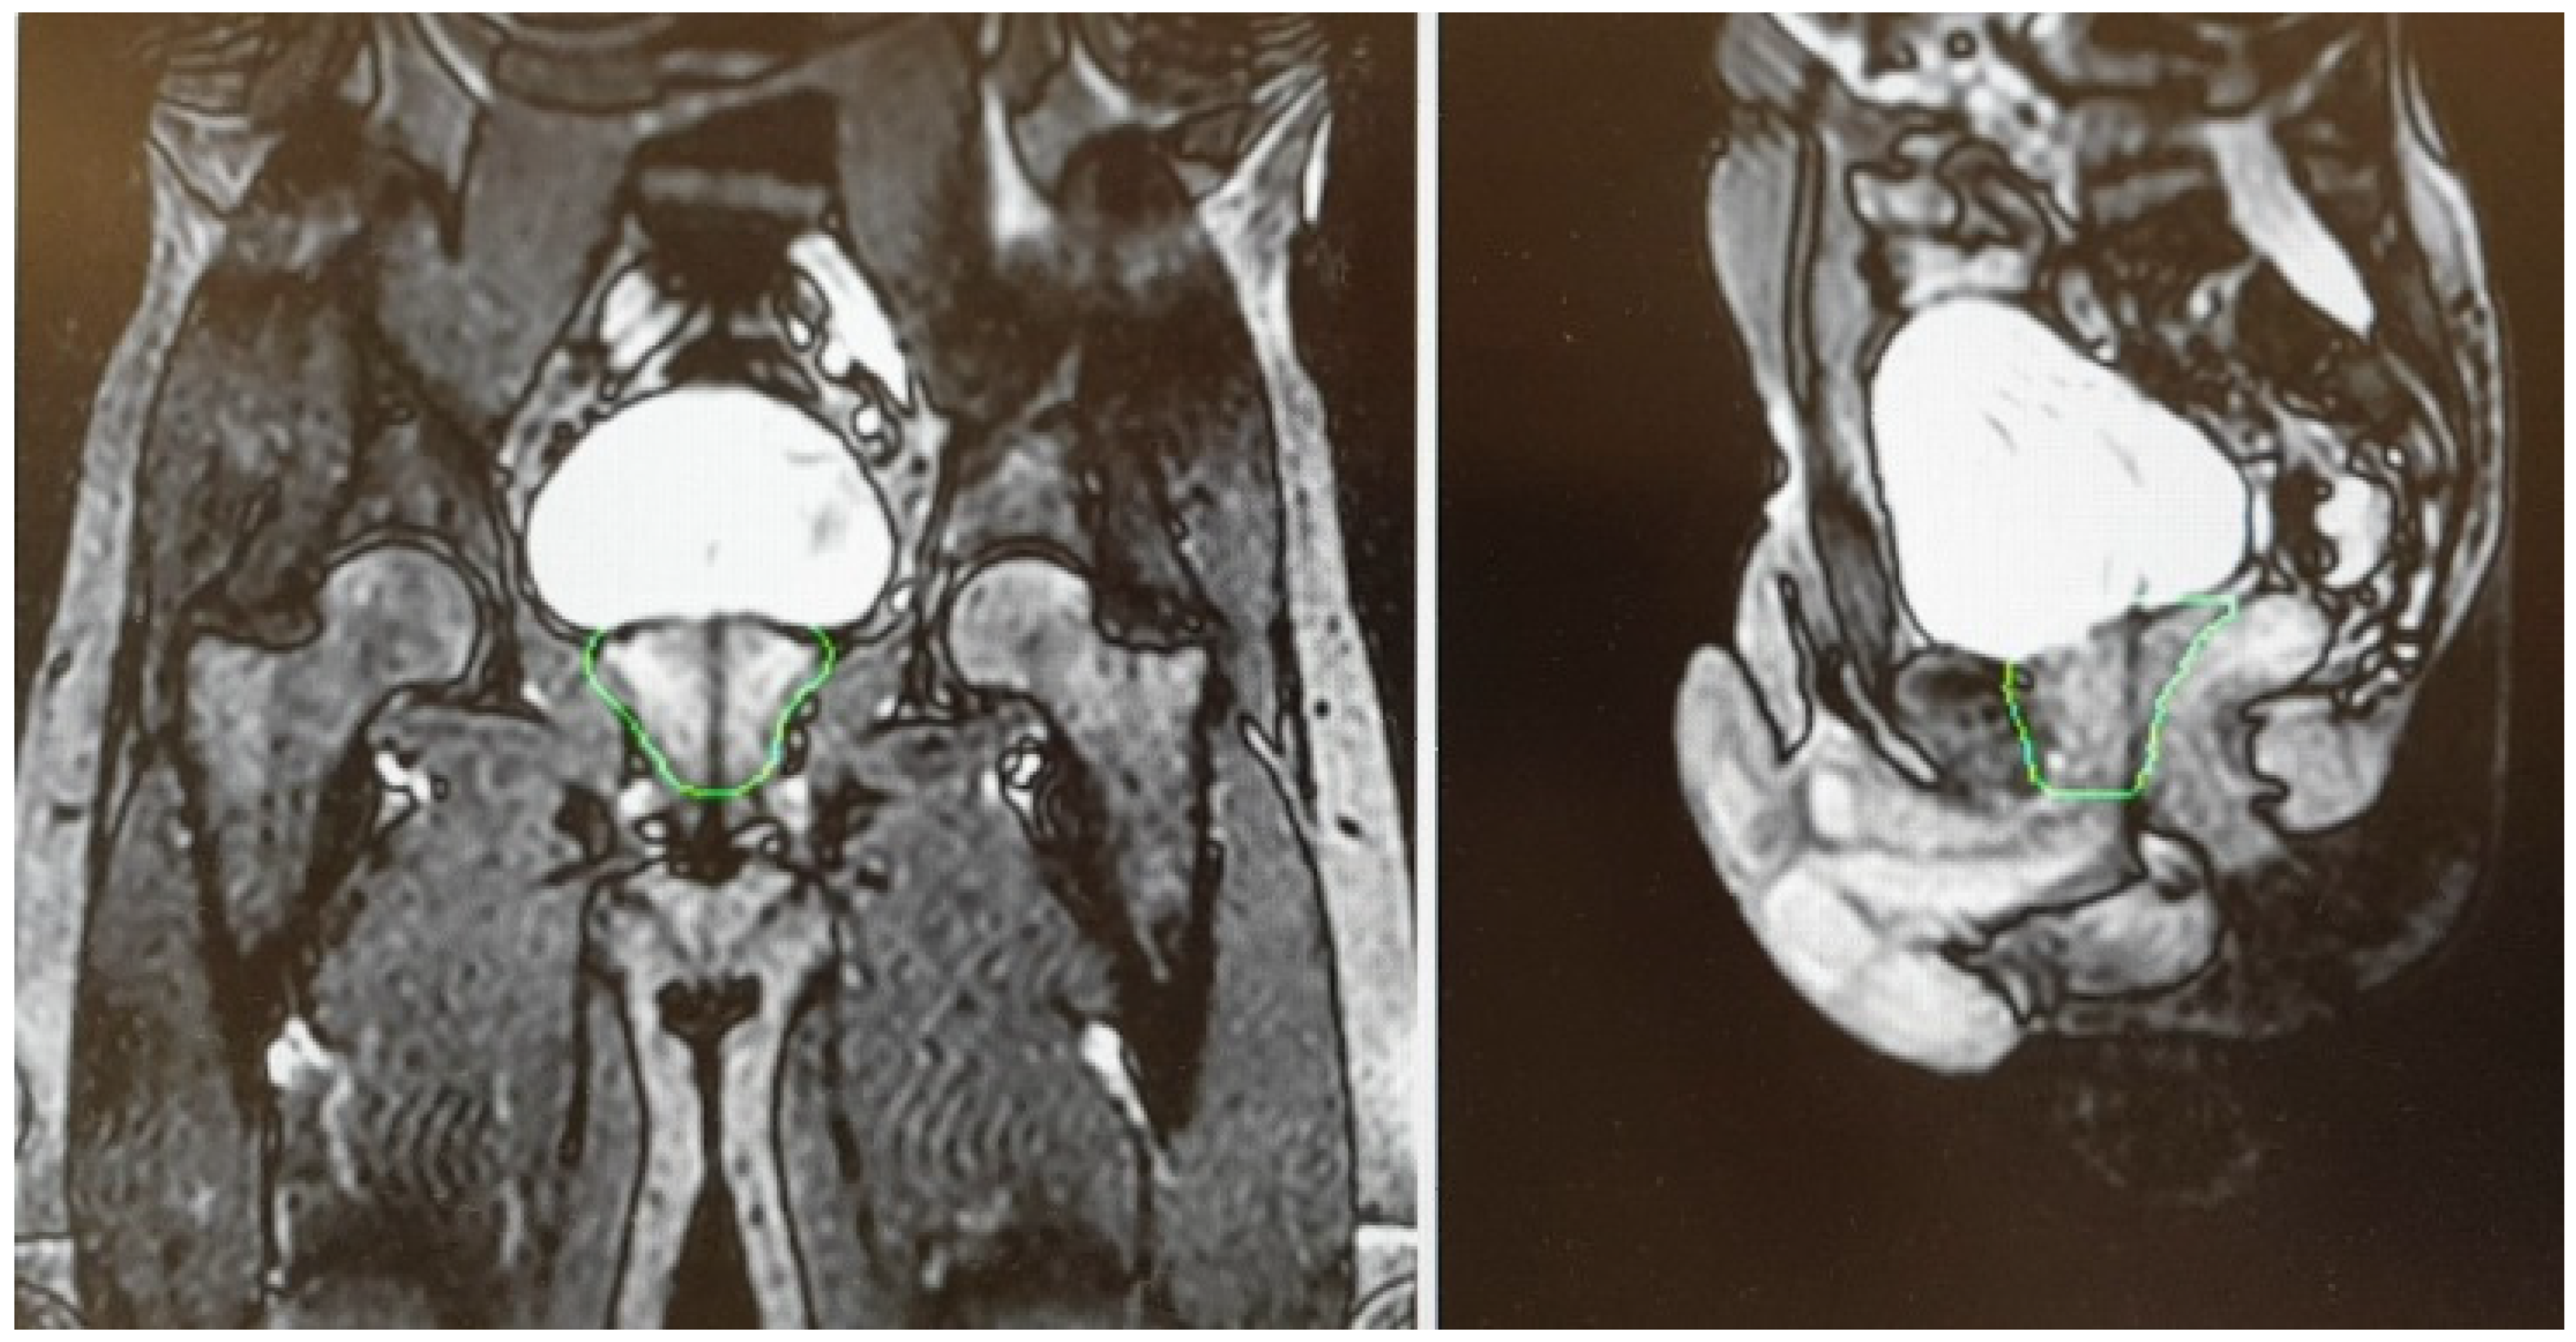

- Spratt, D.E.; Lee, J.Y.; Dess, R.T.; Narayana, V.; Evans, C.; Liss, A.; Winfield, R.; Schipper, M.J.; Lawrence, T.S.; McLaughlin, P.W. Vessel-sparing Radiotherapy for Localized Prostate Cancer to Preserve Erectile Function: A Single-arm Phase 2 Trial. Eur. Urol. 2017, 72, 617–624. [Google Scholar] [CrossRef] [PubMed]

4.3. Sexual Function Preservation